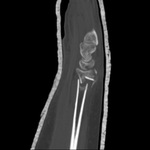

CT scans of the wrist provide excellent detail to assess fracture geometry and articular involvement, as well as degree of comminution

From the collection of Dr Chaitanya S. Mudgal